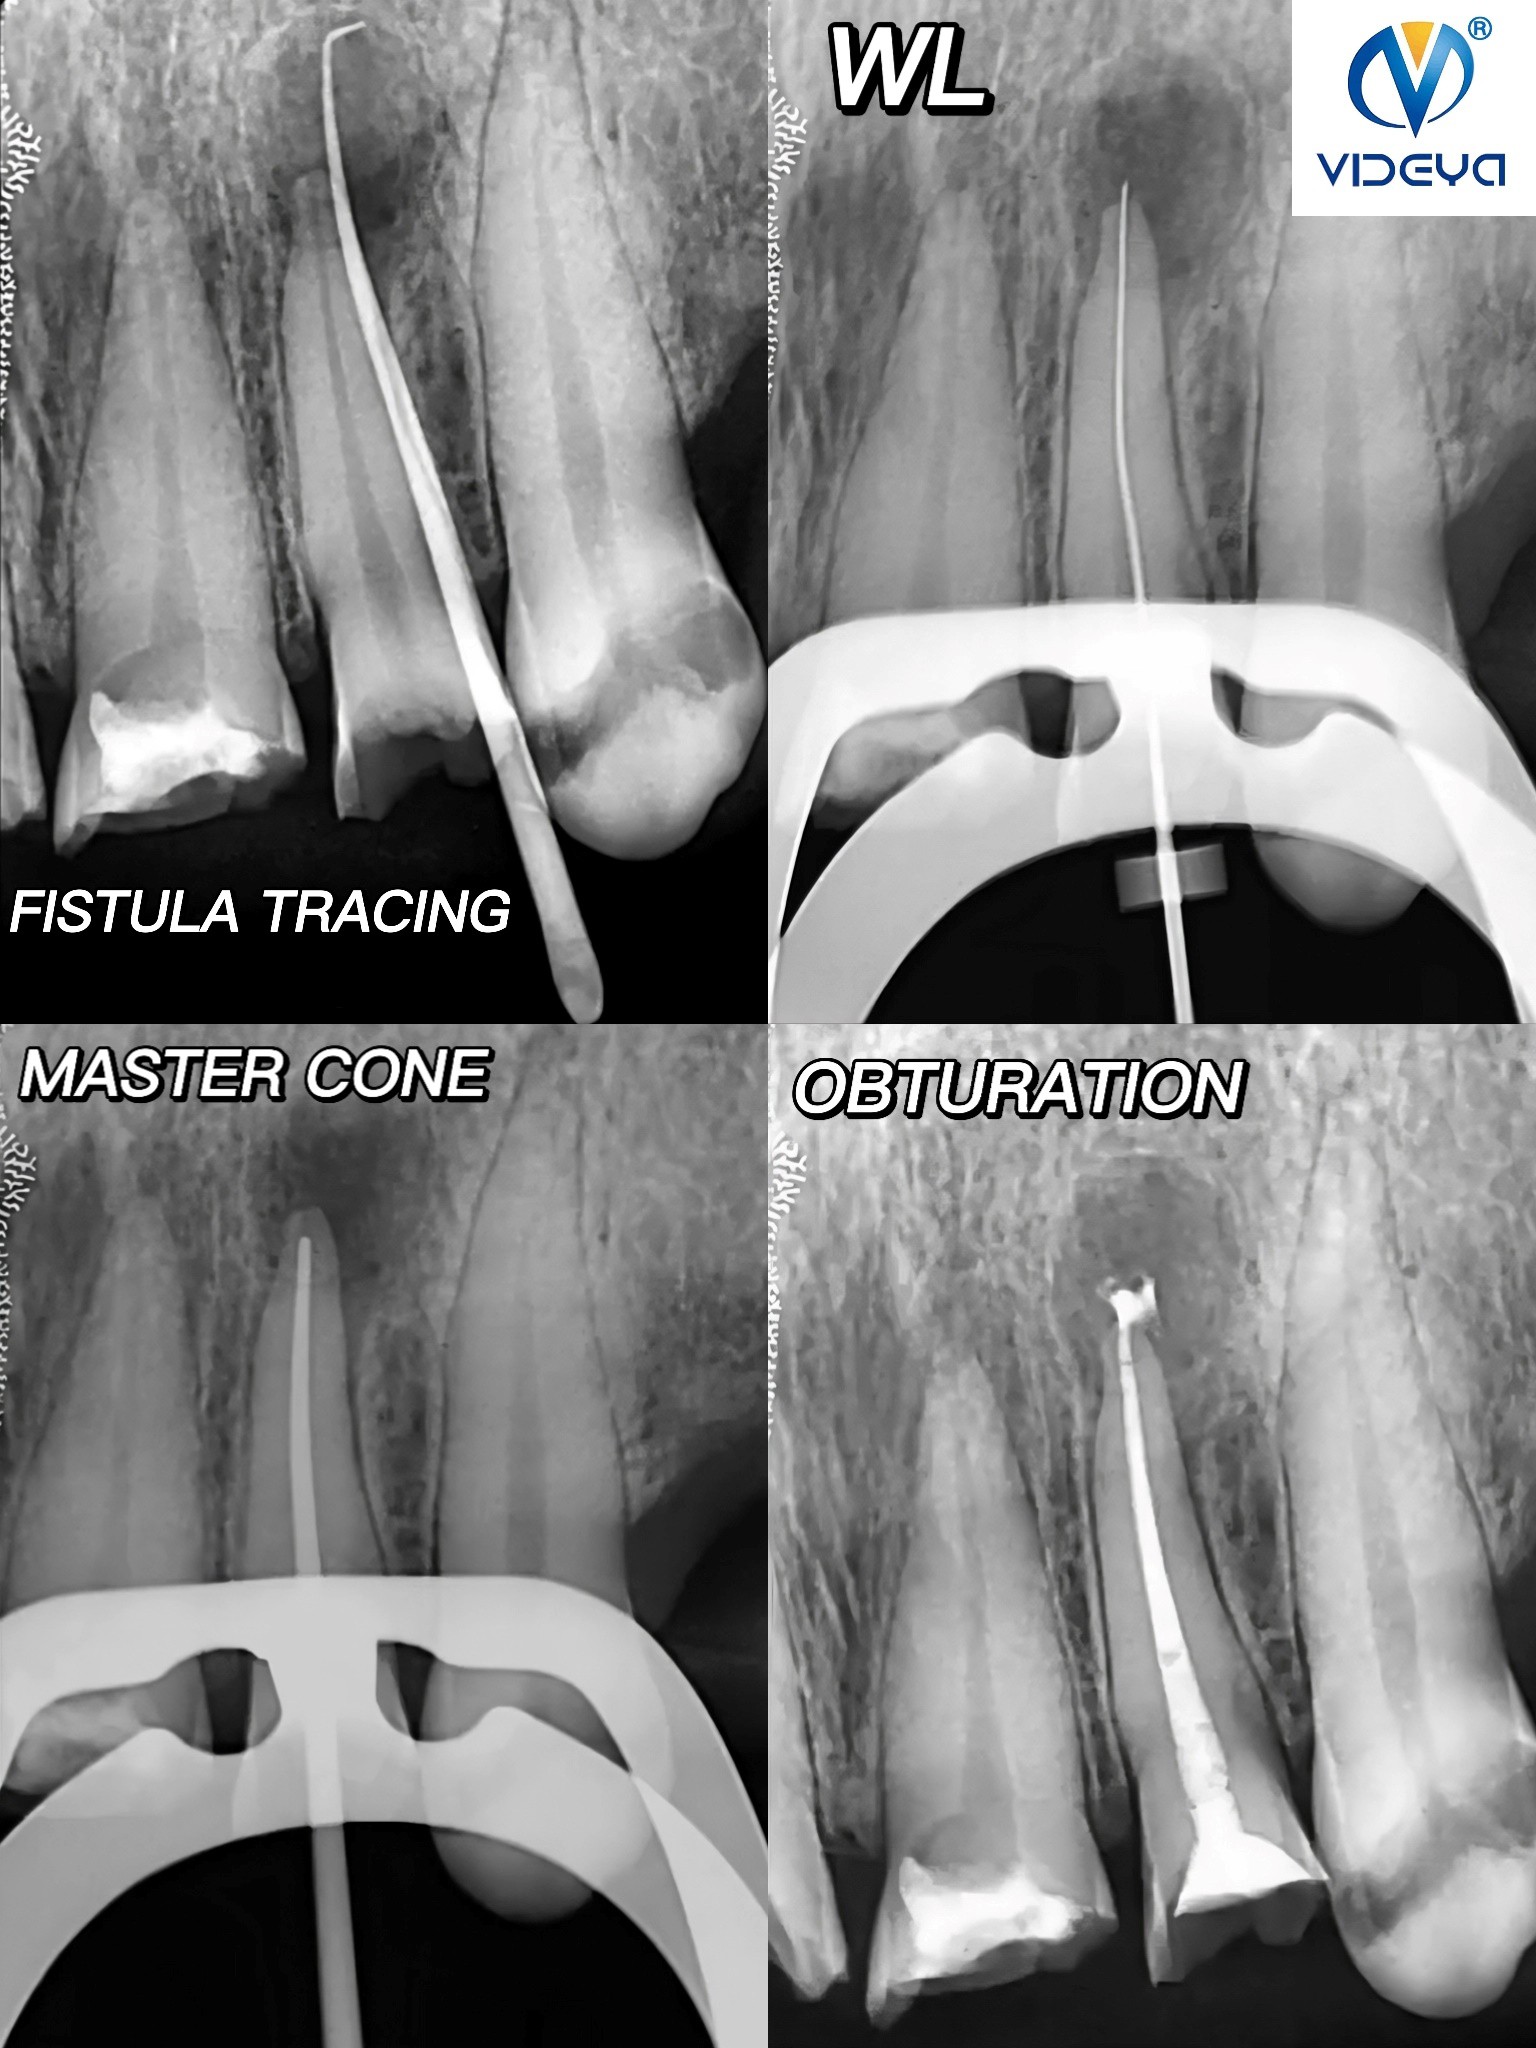

RCT of upper lateral incisor as a part of complete oral rehabilitationUsing Videya Dental TC Blue fies